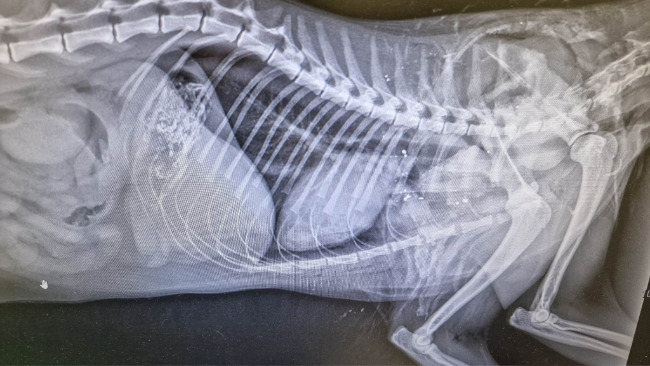

Rudek dostał ciężkiego obrzęku płuc. Rudek miał trochę gorsze płuca niż inni, bo miał je obite przy urazie, były trochę uszkodzone. Na zdjęciach była lekka odma opłucnowa. Cały się zalał, nie pomogły żadne moczopędne leki ani tlen. Umarł.